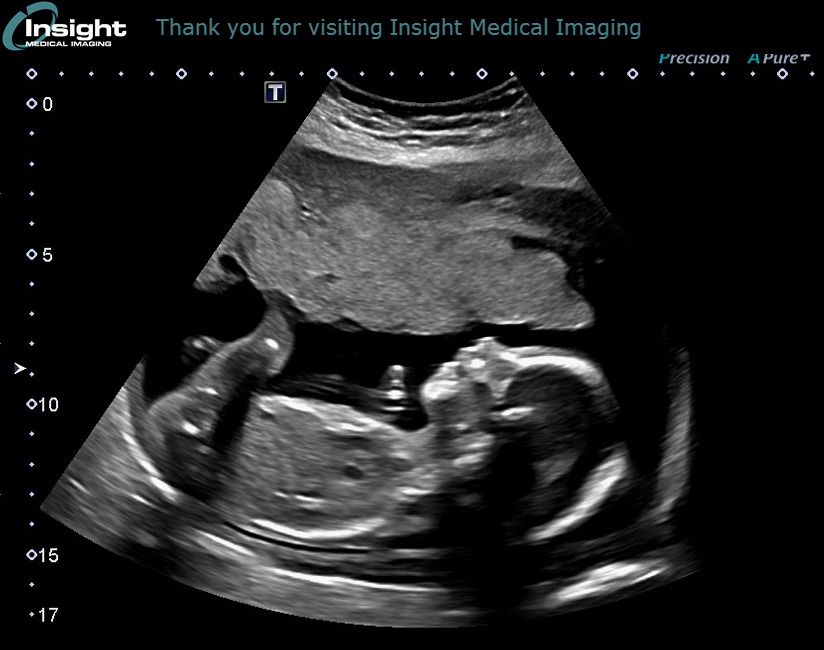

We first learned about Amadea’s condition during the anatomy scan around 20 weeks. For this scan, the ultrasound tech didn’t say much other than “I can’t get clear images of the head”. From there, Rachel was rebooked with a different medical imaging site. For this scan, they revealed that Amadea had something going on. At the time, their response was simply “she is very unlikely to survive birth. We can’t guarantee, but if we could, we would”. We immediately left, completely devastated by the news. We prayed about it and we felt peace about Amadea. We knew she was going to be alright. We continued on as usual.